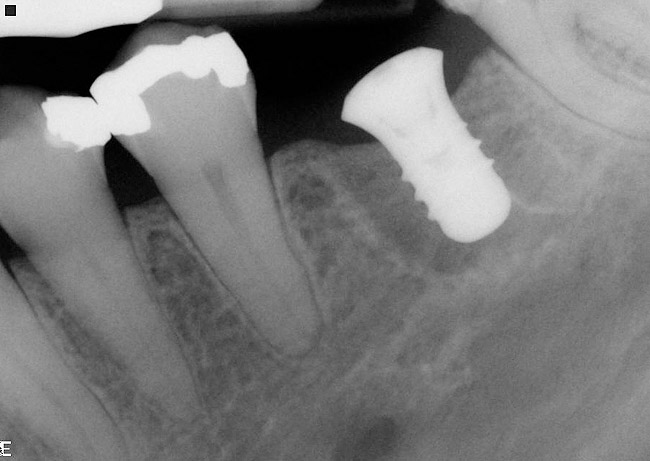

Figure 15  Another view of the implant in the interradicular bone. Note that the mesial and distal aspects of the interradicular septum have been lost. The implant attained primary stability from the buccal and lingual aspects of the interradicular bone.

Figure 15

Figure 16  A radiograph of the restored implant taken after more than 7 years in function demonstrates stable peri-implant crestal bone levels.

Figure 16